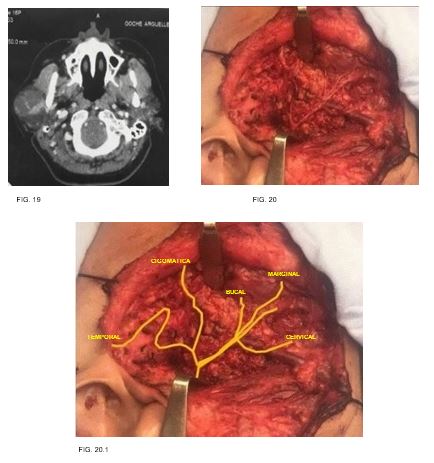

Caso 10: femenino de 45 años de edad, sin antecedentes clínicos de importancia, con tumor parotídeo derecho de 8cm en su eje mayor, resultando en un adenoma pleomorfo. (FIG. 19-20)

11

Referencias anatómicas más importantes para identificación de tronco principal de nervio facial en su salida por agujero estilomastoídeo (FIG. 21):

12